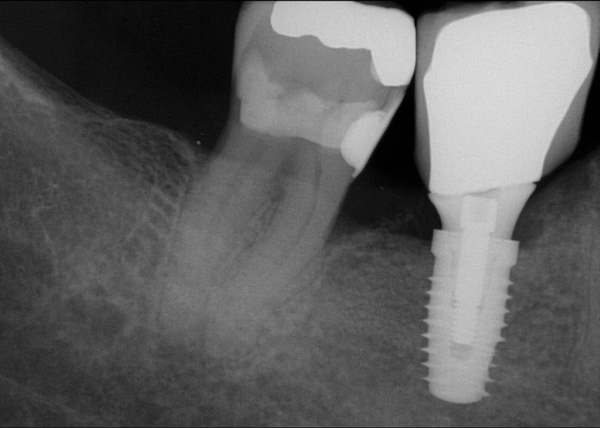

Fig 20. (Case 4) Radiograph of tooth No. 30, which had a hopeless prognosis.

Figure 20

Fig 21. Radiograph of extraction socket. Buccal plate was two-thirds resorbed.

Figure 21

Fig 22. Bone graft was placed in the socket and a d-PTFE barrier was used to cover the graft. The bone graft material was placed beyond the alveolar housing to accommodate shrinkage of graft material and to facilitate attaining a wide alveolar ridge. The barrier was removed after 5 weeks.

Figure 22

Fig 23. Implant inserted in a regenerated ridge after 6 months healing.

Figure 23